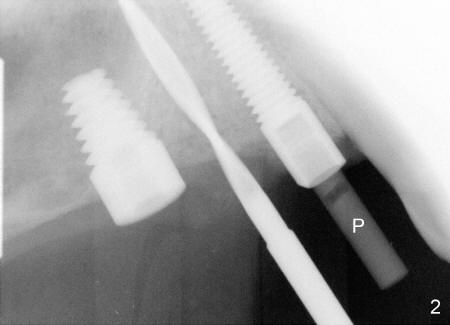

In fact, healing screws had been removed (Fig.1). There is space inside the well of the implant #5 and less obvious in that of #3 (because its wall is thicker). When implants tilt, the opening of the wells is visible (Fig.2-4).

A post guide (Fig.2: P) was inserted to the well of #5 implant as a guide for #4 pilot drill and continually for a drill with larger diameter (Fig. 3 D). Implant placement was a breeze (Fig.4). Two months later, three of the straight abutments (0 degree) were also parallel to each other.

Another beauty of this case is that the pilot drill is used. In case the trajectory is not right, it is easy to correct. In contrast it is not in the later stage of implantation.